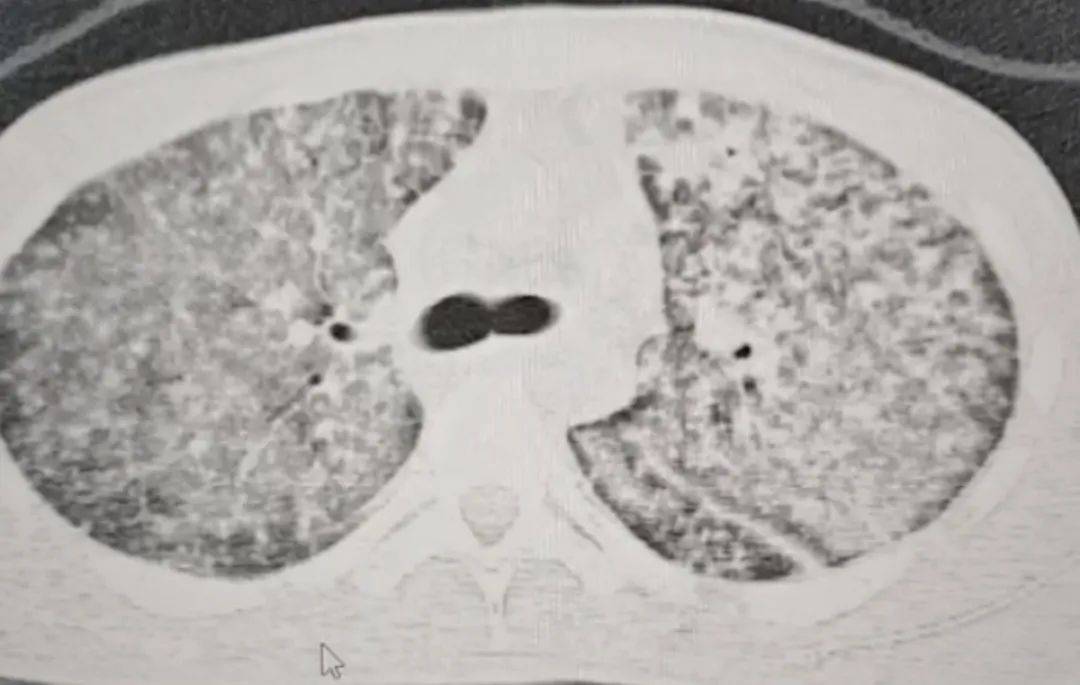

检查结果令医生大为震惊如何代理皇冠信用盘 。肺部 CT 影像显示,小王的肺部几乎全白。

“他来我们医院时,我一看CT,双肺都呈现弥漫性病变,考虑白肺,情况十分危急如何代理皇冠信用盘 。” 河南省胸科医院结核内科六/ 感染危重症病区主任梁瑞霞向大河报·豫视频记者讲述,小王因肺部感染引发了急性呼吸窘迫综合征。

三天后,小王的生命体征逐渐趋于稳定如何代理皇冠信用盘 。十天后复查肺部CT,病区有明显改变。